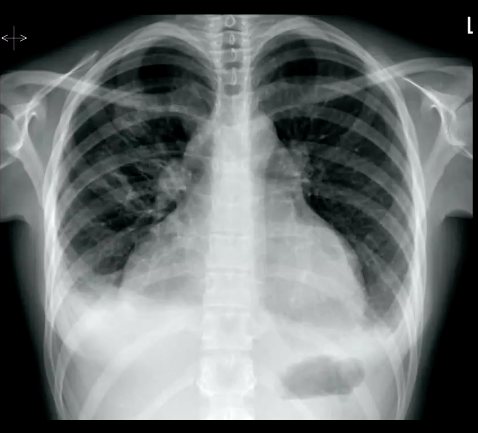

What signs of TB infection are on this CXR?

What type of TB presentation is shown in the CXR?

Miliary TB shown, nodular opacities, with diffuse spread of mycobacterium throughout the lung tissue (this will also be spread diffusely throughout other body tissues).

CT scan will show this even more distinctly.